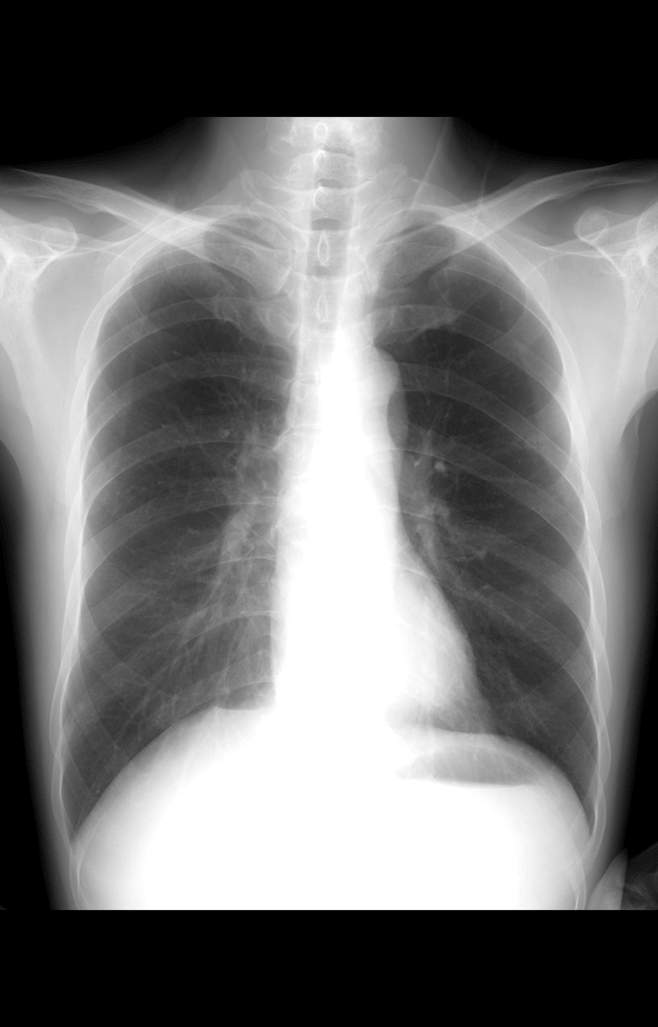

多功能诊断专用动态DR

太阳成集团tyc122cc入口科技全新设计的第四代床式动态DR,集拍片、透视、造影、全身拼接、尘肺体检于一体,一机多能,真正意义上实现全科室应用,提升医院实际效益。

高清动态平板探测器

搭载自主研发超清大视野动态平板探测器,600微米碘化铯大幅提升X线转化效率,独特的非晶硅阵列与高速读取集成电路紧密协作,轻松实现多帧率透视与高清点片。

专业的影像处理系统

“腾灵”系列搭载的IEAE影像处理系统,具备多项发明专利。本系统采用多频域图像处理技术,其6大核心处理模块使影像具有优秀的一致性、柔和性、空间层次感和纹理细腻度,为用户精准诊断病灶奠定了坚实的基础。